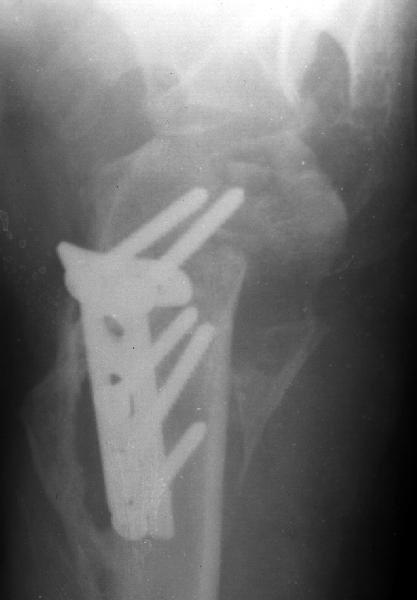

Мужчина 25 лет 16 августа 2002 г. в автоаварии получил перелом шейки плеча (снимок 1); 5 сентября в городской больнице выполнен остеосинтез пластинкой (снимок 2).К настоящему времени попал к нам на разработку ввиду выраженной контрактуры плечевого сустава. В течение последнего месяца беспокоят умеренные боли в области плечевого сустава, усиливающиеся при разработке, еще и торчит край пластинки. Нынешняя рентгенологическаякартина на снимках 3 и 4. Головка плеча уменьшается, сращение сомнительное.Кроме удаления пластинки, что еще на сегодня целесообразно сделать?Заранее спасибо.

2.Пластинка , на мой взгляд, худшее решение для перелома шейки плеча. Сама пластинка слишком груба и массивна, целая слесарня в очень чувствительной для повреждений суставе.

Переломовывих плеча сложная проблема и технически не уверен как для коллег, но для меня сколько я не встречался, технически сложно *вытянуть* вывихнутую головку из-под впадины. Последнее время не применяю пластины для фиксации перелома, а использую спицы и проволочную петлю (тем более часто и густо спонгиозные винты не держатся в головке прочно).